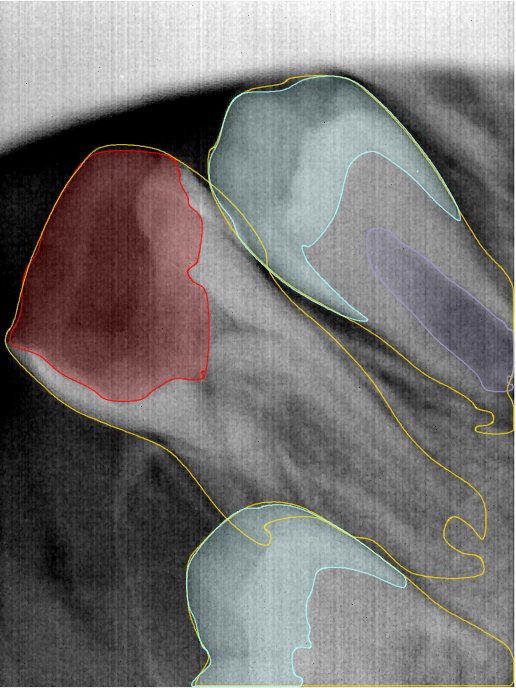

第二版算法问题测试

| 第一版 | 第二版 | 是否解决 | |

|---|---|---|---|

![]() | ![]() ![]() 边角识别有问题 龋齿识别不全 牙髓识别不全 | ![]() | 解决 |

![]() | ![]() 边角识别有问题 识别信息有误 自查(牙冠识别不全) | ![]() | 解决 |

![]() | ![]() ![]() 边角识别有误 大范围填充识别遗漏 | ![]() | 解决 |

![]() | ![]() 识别信息不全 | ![]() | 解决 |

![]() | ![]() ![]() 边角问题 牙胶识别不全 牙冠识别不全 | ![]() | 解决 |

![]() 换图片 | ![]() | ![]() 牙冠部分稍微白了一些就识别成小范围修补,部分判断异常 | 部分解决,修复类略敏感,牙冠部分稍微白了一些就识别成小范围修补,部分判断异常。 |

![]() | ![]() ![]() 牙冠识别不全 牙髓不全 根尖炎龋齿识别有误 | ![]() | 解决 |

![]() | ![]() | ![]() | 解决 |

![]() 换图片 | ![]() | ![]() | 解决 |

![]() | ![]() 牙冠识别有误 | ![]() | 解决 |

![]() 换图片 | ![]() ![]() 边角识别有误 | ![]() 修复类敏感 | 部分解决,图像过白,导致修复类判断异常。 |

![]() 换图片 | ![]() 牙冠识别不全 | ![]() 修复类敏感 | 部分解决,图像过白,导致修复类判断异常 |

结论:修复类出现了不鲁棒的情况,后续需要加入轮廓的扩充数据进行增强。